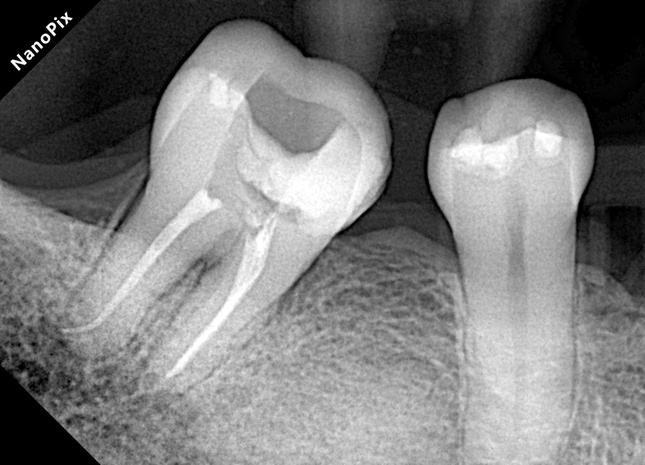

- Imagen de RX asociada a periodontitis apical.

- Diagnóstico: Necrosis pulpar y periodontitis apical sintomática.